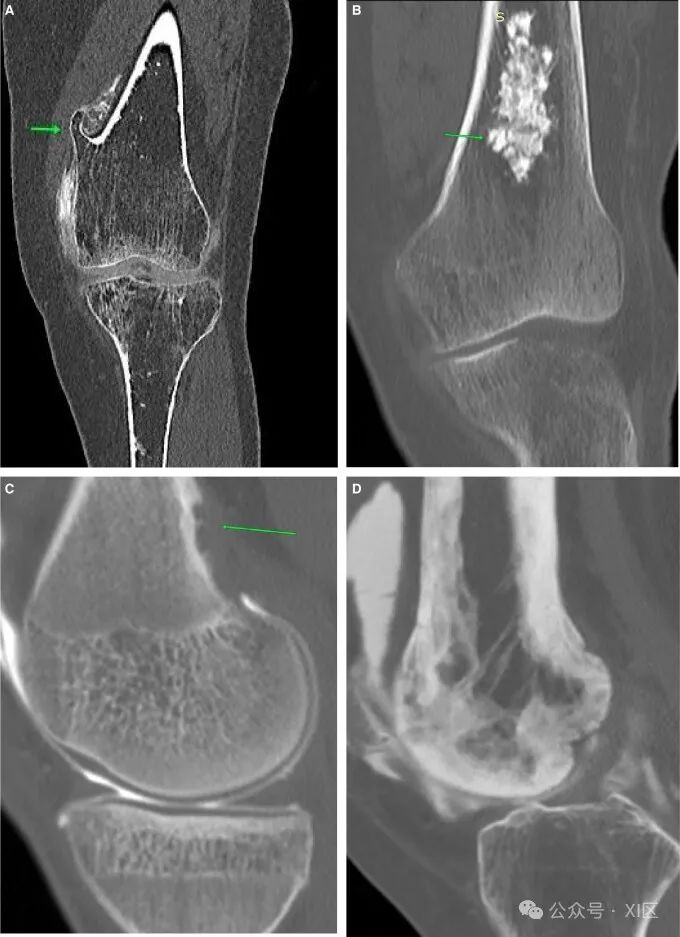

关节造影检查可发现偶然的骨肿瘤。在注射造影剂之前,应仔细筛查计划前图像中的任何骨骼病变。常见的成骨性良性肿瘤包括骨质外生瘤(图10A)、软骨瘤(图10B)、骨化性纤维瘤和纤维皮质缺损(图10C)。当对膝关节进行疼痛成像时,也可能偶然发现罕见的病理,如佩吉特病(图10D)。膝关节的自发性骨坏死表现为膝盖疼痛。预先计划的CT显示局灶性骨质增生,但无骨软骨缺损。对比后图像显示了骨软骨缺损的完整范围(图11A和B)。先前的关节造影(图11C)可用于显示骨软骨区域的急性变化。

图10 骨肿瘤:(A)典型骨软骨瘤(箭头)。(B) CT扫描中发现的对侧膝关节典型软骨瘤(箭头),随后进行了成像。(C) 偶然发现的纤维皮质缺损(箭头)。(D) 典型的股骨 Paget 病。

图11 自发性骨坏死:(A)股骨内侧髁(箭头所示)的深部急性凹陷,伴有血性抽吸液。(B) 近一年前的关节造影图像,显示股骨内侧髁正常。滑膜肿瘤